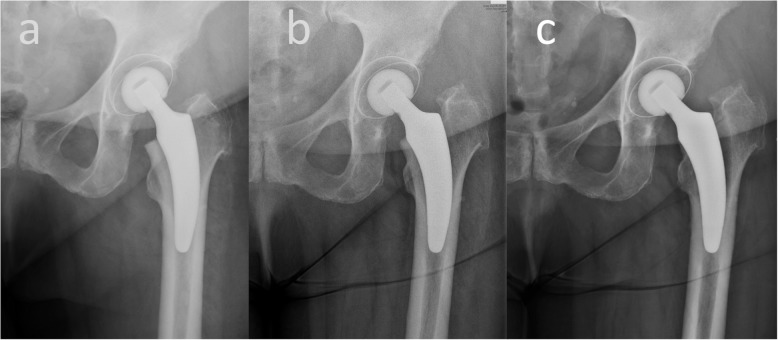

Fig. 2.

Aseptic loosening of the stem in one patient. The x-ray images of the case, in which an aseptic loosening was diagnosed is depicted. a Postoperative, b 3 months and c 6 months postoperative images are presented